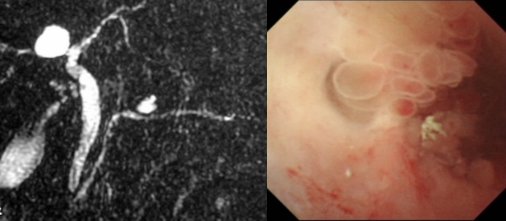

内視鏡を用いた検査として、超音波内視鏡検査(EUS)や内視鏡的逆行性胆管膵管造影(ERCP)があります。EUSは内視鏡を用いて胃や十二指腸から超音波で観察する検査で、IPMNの内部の構造や膵管の状態を詳細に観察できます。ERCPは入院で行う内視鏡検査で、特にIPMNの悪性化が懸念される場合に、膵管内の造影や膵管鏡での観察、膵液や膵管の細胞の採取などを行います。膵液や膵管の細胞の悪性度を判定し、悪性化が疑われる場合には、手術の必要性について検討します。

左図:MRCP検査 右図:ERCPによる膵管鏡検査